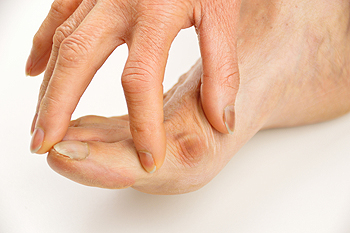

- Pain around the heel or arch area

- Trouble standing on the tip toe

- Swelling around the inside of the ankle